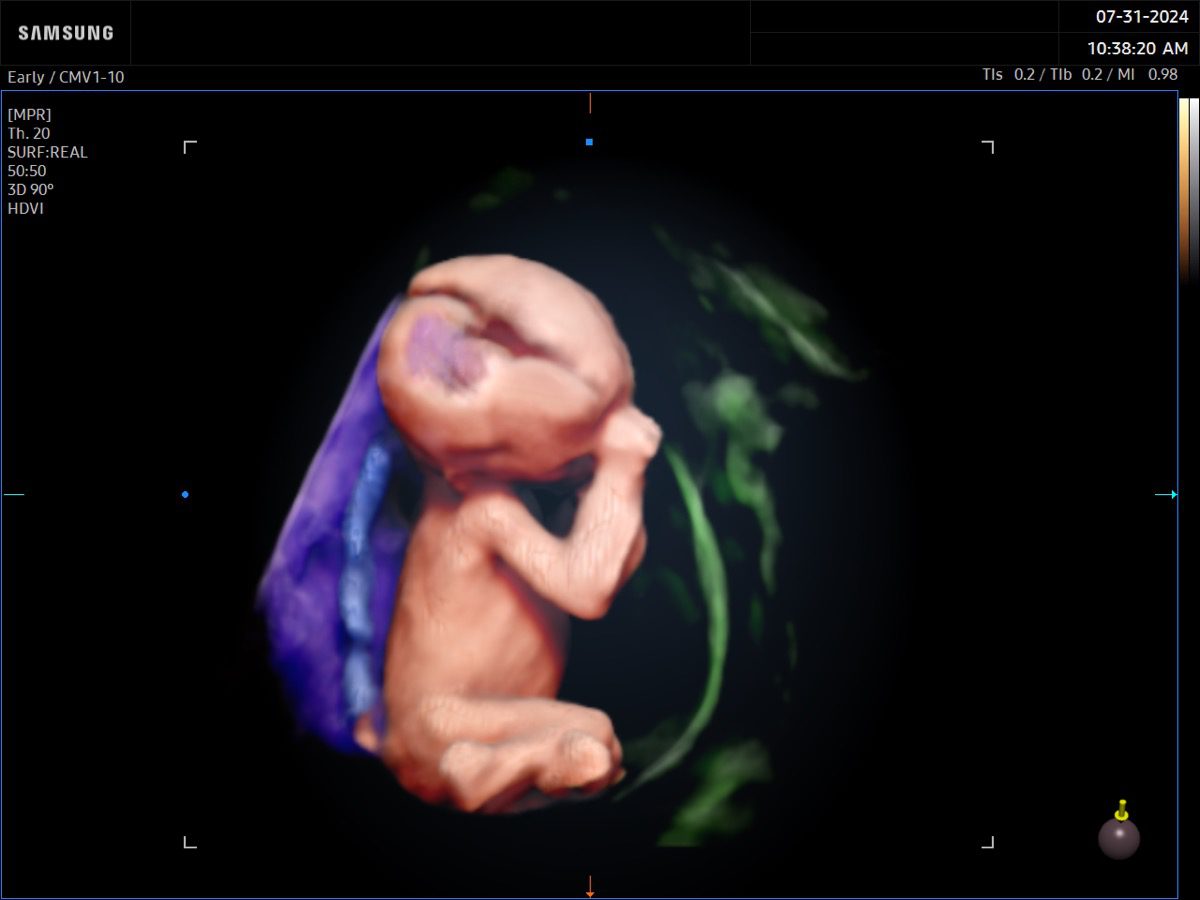

Comprehensive, advanced and expert MFM care for high-risk pregnancies

- Fetal anomalies